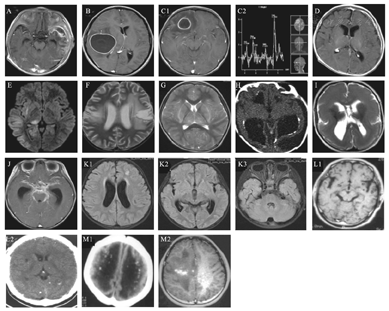

化脓性脑膜炎(图3A)增强CT时软脑膜强化,但无特异性,头颅MRI FLAIR成像对脑膜炎最敏感。脑实质化脓性感染性脑炎,CT低密度影,MRI T1WI低信号,T2WI和FLAIR高信号。脑脓肿(图3B、C1)形成时MRI具有典型性特征,脓肿多位于灰白质交界处,早期脓肿形成特征是化脓性脓肿周围形成良好的胶原蛋白壁。晚期脓肿为纤维囊的成熟和增厚以及坏死中心的减小。CT显示病灶周围水肿和低密度的坏死中心,T1WI上坏死中心显示低信号,囊壁显示高信号,周围低信号为水肿影像;T2和FLAIR上为中央高信号,囊壁为低信号[33]。化脓性脓肿需与肿瘤鉴别。薄而规则强化的囊多为脓肿,厚或结节状的囊多为肿瘤。磁共振波谱成像(MRS)(图3 C1、C2)可以区分脓肿和肿瘤,中央坏死区内乳酸、琥珀酸、乙酸、丙氨酸和氨基酸峰是脓肿的标记物,反映了微生物的糖酵解增加,而缺乏胆碱峰[34]。硬膜下积脓(图3D)也是细菌性感染的重要表现之一。

A.左侧颞叶脑膜脑炎;B.脑脓肿;C1、C2.右额叶脓肿及其MRS;D.左侧额顶部硬膜下积脓;E.病毒性脑炎;F.疱疹病毒脑炎;G.甲型流感相关性脑病;H.巨细胞病毒感染及其钙化;I.巨细胞病毒感染神经元移行异常;J.结核感染;K1、K2、K3.隐球菌感染;L1、L2.脑囊虫感染;M1、M2.弓形虫感染。

急性病毒性脑炎CT表现为散在斑片状低密度或大片状低密度影。MRI比CT更敏感,更具有特征性。急性病毒性脑炎由于炎症、水肿及脱髓鞘病变T1WI上呈低信号,在T2WI上表现为散在片状长T2高信号,白质内有指套状大片高信号,多发生于灰、白质交界处。病情进一步进展,灰质出现水肿,在T2WI上呈脑回状高信号。弥散加权像(DWI)(图3E)能比常规序列更早地显示高信号表现的病变区。

单纯疱疹病毒Ⅰ型感染(图3F)是儿童常见的病毒性脑炎。CT典型表现为单侧或双侧的颞叶内模糊低密度,常累及岛叶皮层,严重者同时累及壳核,豆状核不受累[35]。MRI敏感度近90%,表现为因水肿出现T1WI肿胀伴灰白质差异消失,伴有T2/FLAIR皮质和皮质下的高信号。MRI影像更具特征性的表现为颞叶内侧、额叶眶面、脑岛皮层可见长T1、长T2信号。因病变不累及豆状核,豆状核与病变常有刀切样清楚的界线,是其特征性表现之一。病变区早期有出血性表现时,CT上为高密度影,T1WI、T2WI/FLAIR上表现为高信号[36]。

甲型流感相关性脑病(图3G)MRI表现为颅内多发低密度灶或弥漫性异常信号,特征性改变是双侧丘脑对称性异常信号伴肿胀,可累及基底节、脑干、脑室周围白质、壳核和小脑,也可以表现为胼胝体压部的可逆性病变[37]。

巨细胞病毒感染(图3H、I)可引起脉络膜、视网膜炎及脑膜炎,CT上局限于脑室旁,基底节区的颅内钙化为特征性表现[38]。可引起脑梗死、脑萎缩、小脑畸形、积水型无脑畸形等,也可引起神经细胞移行异常、脱髓鞘伴有胶质增生。

颅内结核感染时结核杆菌多积聚于基底池,呈结节状增生,并能延伸到半球裂隙,可沿皮质表面和脑神经延伸。CT与MRI上脑池内有类似软组织的密度影。MRI上在T1WI上信号比脑脊液稍高,T2WI上因和脑脊液信号形似而不能显示。增强扫描时受累的脑池明显强化,在灰白质交界处可见多发具有强化效应的病灶。肉芽肿形成后会合并形成更大的中央坏死性病变。非干酪性结核在CT上表现为低密度影,在T1WI和T2WI/FLAIR上表现为低信号,病灶周围水肿区可有强化影。MRS上脂质和乳酸峰和缺乏氨基酸峰可区别于化脓性脓肿[39]。干酪性结核,脑实质内常有结核瘤,增强扫描表现为环形强化灶。幕上者常为多发,幕下则往往单发。粟粒性脑结核在增强扫描时脑内弥漫性点状和小环状强化灶十分典型。

新型隐球菌脑膜炎(图3 K1、K2、K3)多累及蛛网膜下腔,沿血管周围播散,累及基底神经节、丘脑和皮质下白质。胶状假性囊肿和隐球菌球形成时MRI表现为基底节区多发的囊性病灶,呈脑脊液样信号,无强化表现;也可在MRI表现为环形强化的结节状真菌球[40]。室管膜受累导致一半的病例出现交通性脑积水。

脑囊虫病MRI(图3 L1)敏感性显著高于CT(图3 L2)且能显示分期,小囊性病灶多位于大脑皮质,基底神经节或蛛网膜下腔[41]。脑实质型脑囊虫病最常见,CT上表现为小圆形低密度内有一点状稍高密度的头节。MRI T1WI上表现为小圆形低信号,有偏心的点状中等信号的头节,囊壁很薄,T2WI上则可见囊呈小圆形高信号,其内头节呈稍低信号,周围无反应性脑水肿。随着时间延长,CT可见低密度的小囊性病变,周围有低密度水肿区。T1WI上灰白质交界区大小不一的片状低信号,其边缘部分可见低信号小囊状病变,T2WI上为片状高信号,呈指套状向灰质衍生,小囊状病变中央为高信号,周围为低信号环。增强扫描可见环形强化,脑水肿区无强化。肉芽肿期,T1WI上为小圆形低信号,T2WI上囊虫呈稍高信号,伴或不伴脑水肿。最后囊虫肉芽肿完全钙化,CT上呈点状高密度[42]。

弓形虫感染:神经影像学检查显示多发病变,累及基底神经节、丘脑和皮质髓质交界处。中央坏死部位CT上为低密度影,MRI(图3 M1、M2)在T1WI上高信号,T2WI上低信号。30%的病灶表现为偏心结节增强,称为"偏心靶征"[43],是弓形虫病非常特殊的标志。